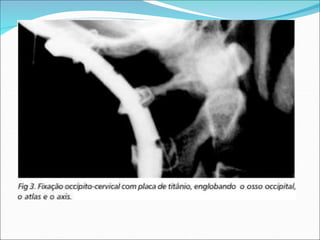

LUXAÇÃO ATLANTO-OCCIPITAL

 Tratamento:

 A artrodese occipito-cervical, após a redução da lesão

por meio de tração, é o tratamento de escolha devido à

instabilidade desse tipo de lesão.

 Técnica:Após a redução, são feitos o amarrilho

metálico e a artrodese entre os arcos de C1 eC2